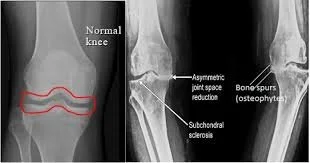

This is a good picture to show decreased movement/ glide in the joint space when loaded by the body in standing.